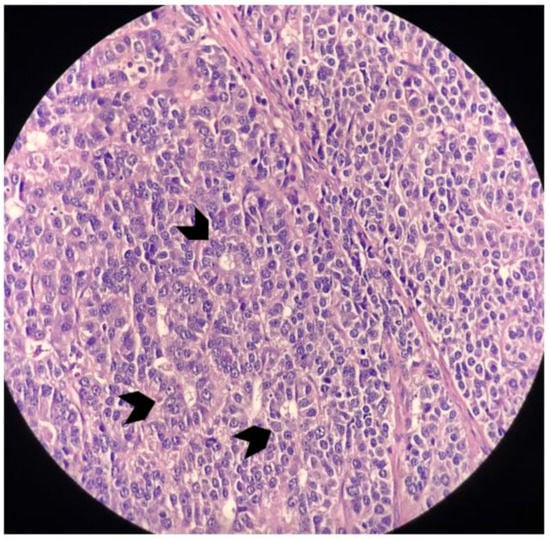

2. Case Report